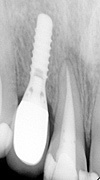

症例 13

① 前歯1本がないところにインプラントを埋め込んだレントゲン写真です。

② 最終的な歯が入りメンテナンス中のレントゲン写真です。

30才代 女性

総額:42万円(税別)

治療期間:4ヵ月

リスク副作用:経年的に骨が吸収すると審美障害が生ずることがあります。